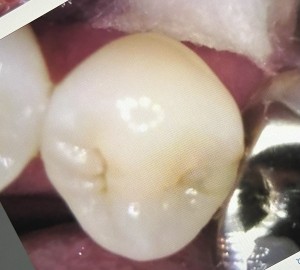

治療前の歯は以下のような状態でした。

1日目 虫歯を取り除き、プラスチックで成形した後、型取りを行います。

2日目 セラミックを接着性のセメントで装着します。